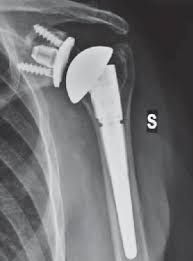

위의 사진과 같이 기존의 인공관절은 humerus 의 골두를 제거하고 glenoid 모습과 비슷하게 작동하는 원리로 인공관절이 되었으나 최근에는 humerus head 의 medialization 효과와 deltoid muscle lever arm의 증가로 더 효과가 있는 reverse shoulder arthroplasty 가 많이 시행되고 있습니다. 1990년대부터 수술을 시작했으니 30년 정도 지난 수술법입니다.

쉽게 생각하면 Convex 와 Concave가 반대로 된 구조라고 생각하면 됩니다. 회전의 중심(Center Of Motion)이 좀더 아래와 안쪽에 위치한 생역학적 장점을 갖고 있습니다.